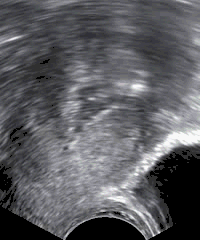

Utrasound of the uterus performed because of postmenopausal bleeding. In serial images, polyps would be more immobile than freely moving debris within the uterine cavity which are seen in the image.

The cause of the bleeding can often be discerned on the basis of the bleeding history, physical examination, and other medical tests as appropriate. The physical examination for evaluating vaginal bleeding typically includes visualization of the cervix with a speculum, a bimanual exam, and a rectovaginal exam. These are focused on finding the source of the bleeding and looking for any abnormalities that could cause bleeding. In addition, the abdomen is examined and palpated to ascertain if the bleeding is abdominal in origin. Typically a pregnancy test is performed as well.[32] If bleeding was excessive or prolonged, a CBC may be useful to check for anemia. Abnormal endometrium may have to be investigated by a hysteroscopy with a biopsy or a dilation and curettage.